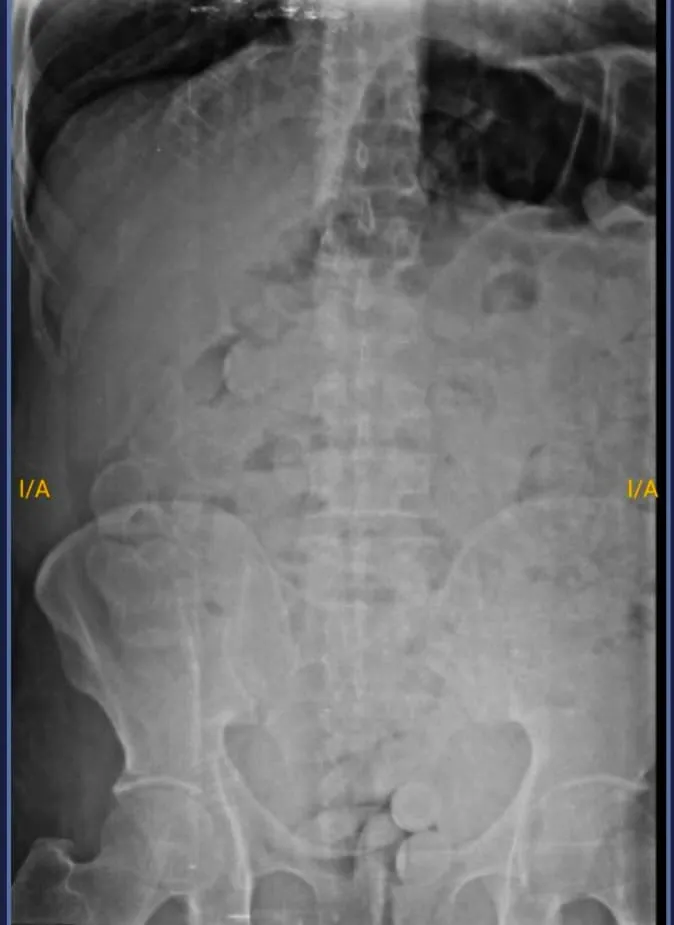

Ante esa situación, a los fines de preservar la salud de ambas personas, por orden de la Unidad Fiscal Federal de Jujuy, los involucrados fueron trasladados hasta el Nosocomio Jorge Uro de la ciudad de La Quiaca en donde les realizaron placas radiográficas y pudieron observar la presencia de cuerpos extraños.

Luego de que ambas personas evacuen las 182 cápsulas ingeridas, los gendarmes realizaron la prueba de campo Narcotest que dio como resultado positivo para cocaína con un peso total de 2 kilos 184 gramos.